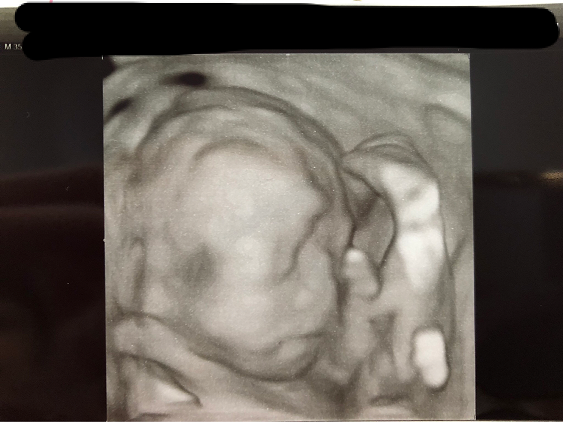

22週0日(22w0d・男の子)|3姉弟ママ さん(29歳)

エコー写真撮影時のエピソード:

3回目の妊娠。上の子同様、つわりも何もなくとっても健康妊婦。初めての3Dエコーでの写真。胎盤に気持ちよさそうに抱きついてる我が子をみて、愛しさがましました。無事に産まれてエコーのときのように抱っこで眠る我が子をみて幸せを感じてます。3Dエコーはリアルでちょっと怖い感じかなと思ってたのですが、自分の子供はやはり可愛く思えるものですね笑